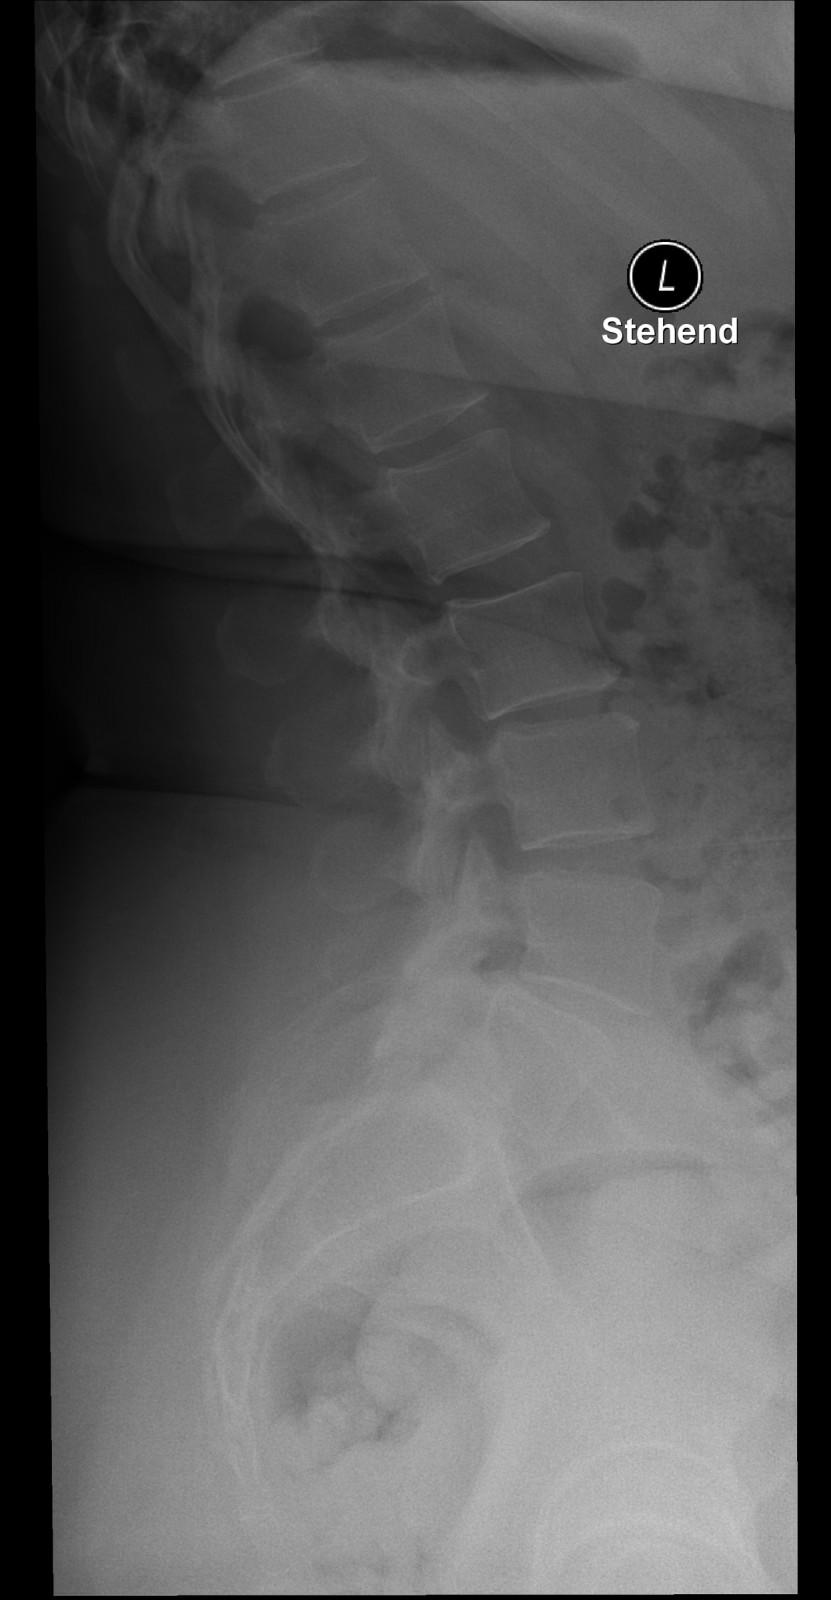

Röntgenfall des Monats Dezember 2017 mit Auflösung

45 jährige Patientin Klinische Angaben: Seit gestern tief lumbale Schmerzen ohne Trauma. Druckdolenz untere LWS und ISG bds.

Bild vergrössern